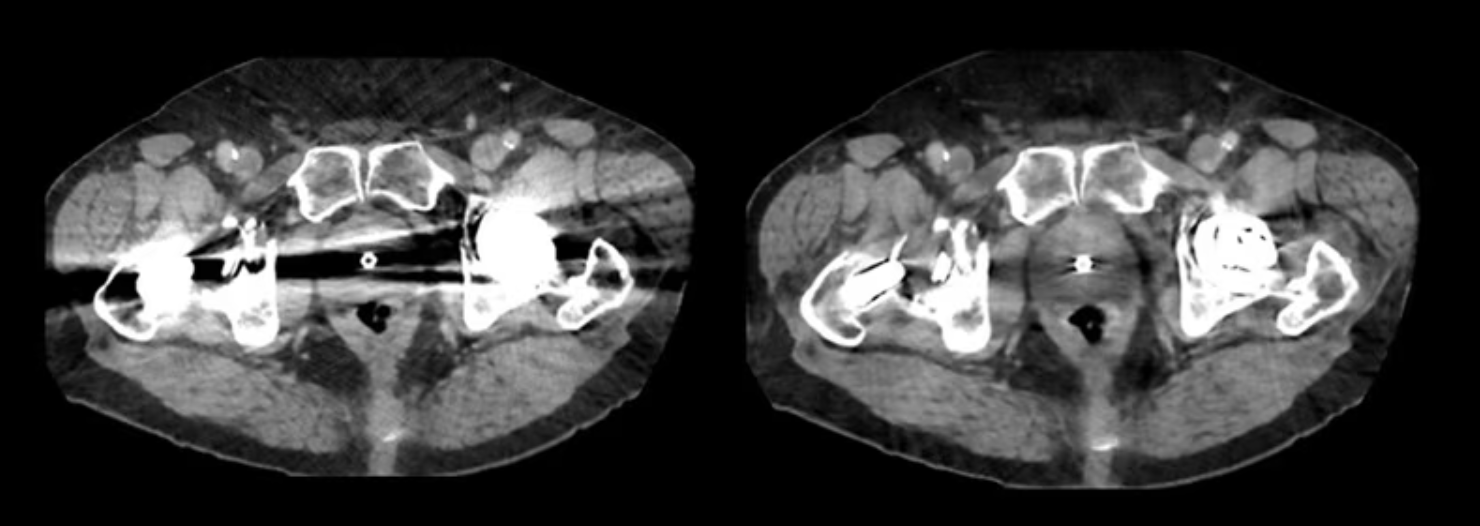

В клинической практике металлические конструкции часто создают выраженные артефакты на КТ изображениях. Это может затруднять оценку окружающих тканей и снижать информативность томографии. В системе реализована технология Smart MAR (Metal Artifact Reduction), предназначенная для уменьшения артефактов от металлических объектов при выполнении исследования.

Алгоритм анализирует данные реконструкции и корректирует области, где возникают искажения из-за высокоплотных материалов. В результате уменьшается выраженность полосовых артефактов и улучшается визуализация анатомических структур рядом с имплантами и протезами.

Smart MAR уменьшает выраженность полосовых артефактов, сохраняя структурную детализацию костей и мягких тканей. Слева без MAR, справа с MAR